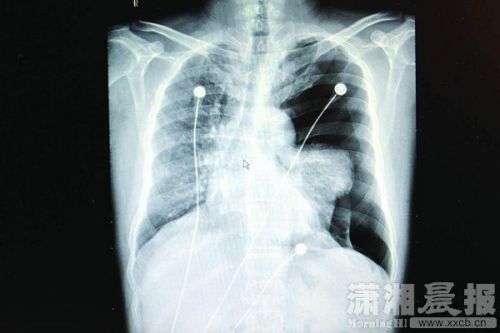

長沙市中心醫院。近日,45歲男子李某K歌太猛,導致左側肺大皰破裂引發了氣胸。圖/瀟湘晨報記者陳勇

“患者入院時呼吸、講話很困難,不能平臥,左手緊緊捂著胸口,有明顯的呼吸困難、胸痛等癥狀。緊急檢查發現,其左側重度氣胸,左肺已壓縮60%以上,心臟受壓移位;若不及時處理,很可能危及生命。”長沙市中心醫院胸心外科副主任醫師彭建明介紹,人的胸膜腔是密閉的、不含空氣的潛在性腔隙,在一些先天因素的影響下,有部分小肺泡會逐漸融合成一個巨大的、沒有氣體交換功能的肺大皰,導致肺組織彈性下降;當劇烈咳嗽、踢足球、提重物、大笑、K歌等用力過猛活動時,肺內壓力突然增加,很可能導致肺大皰破裂發生氣胸,氣體進入胸膜腔導致肺葉被壓縮,從而引起呼吸困難,嚴重時可危及生命。彭建明說:“醫生在全麻胸腔鏡下為李先生行微創手術,術后恢復情況良好,順利出院。”